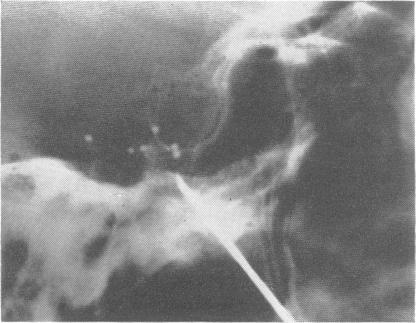

TRIGEMINAL ROOT AND GANGLION INJECTIONS USING PHENOL IN GLYCERINE FOR THE RELIEF OF TRIGEMINAL NEURALGIA.

J Neurol Neurosurg Psychiatry. 1963 Aug;26(4):345-52. doi: 10.1136/jnnp.26.4.345.